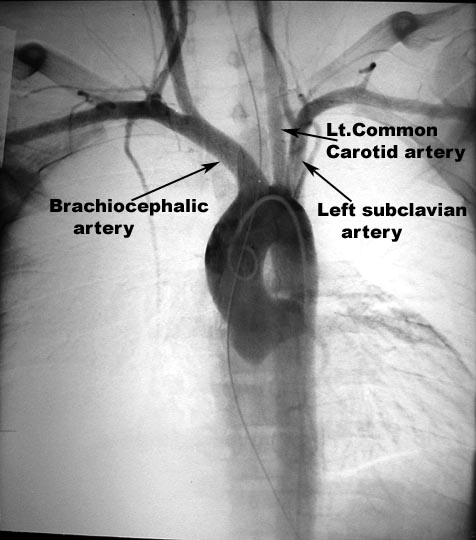

- Brachiocephalic arteryLCCALeft subclavian artery

- Branches

- Appearance in